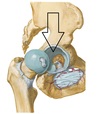

Iliofemural ligament